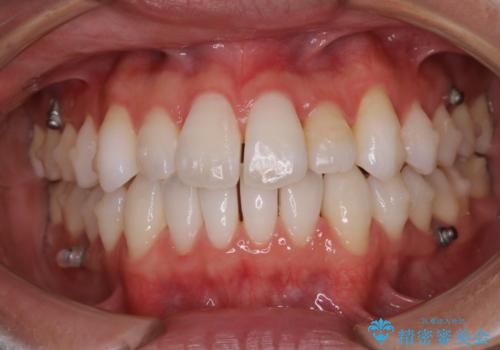

【非抜歯】八重歯を治す マウスピース矯正

- 前歯のガタつきの治療を主訴にご来院されました。

目立たない装置をとのご要望があったため、検査結果をふまえてインビザラインでの非抜歯矯正を行うこととなりました。

抜歯をせずとも笑った時の歯の見え方が劇的に変化していることが分かります。